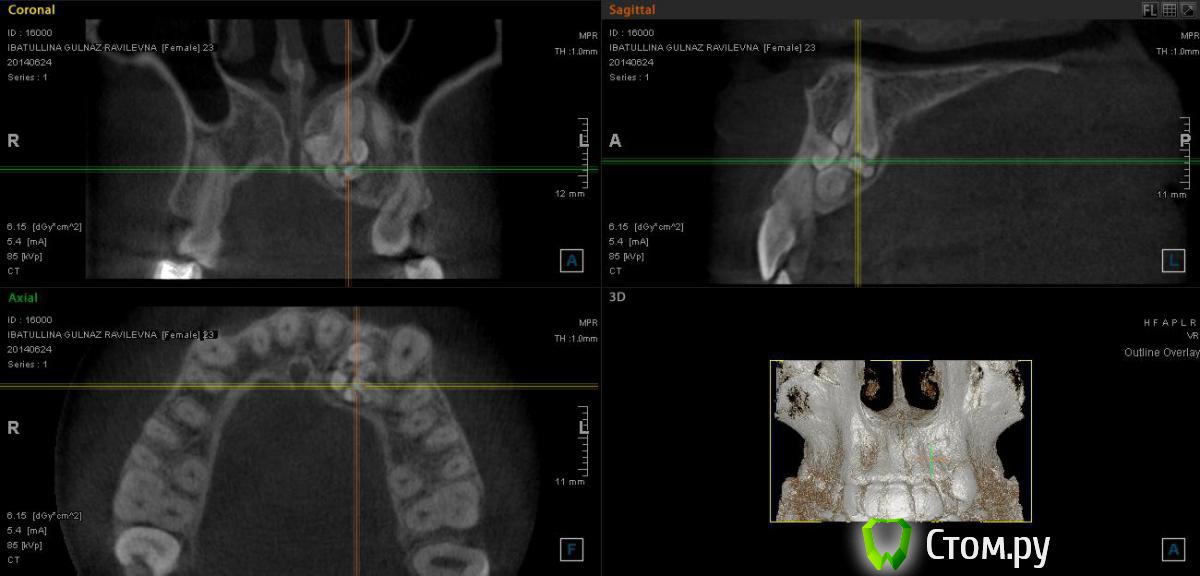

Фазлиев Азат Ильдусович Опубликовано 25 сентября, 2014 Поделиться Опубликовано 25 сентября, 2014 не могу не поделиться)) 4 Ссылка на комментарий

Фазлиев Азат Ильдусович Опубликовано 16 мая, 2016 Автор Поделиться Опубликовано 16 мая, 2016 чем закончился случай?пока только удалением одонтомы Ссылка на комментарий